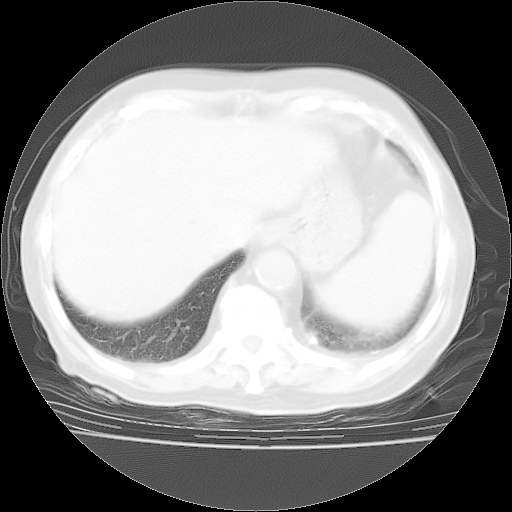

4月28日肺部CT——再次出现类似去年5月9日——透光度降低,“间质性”改变。

4月28日肺部CT——再次出现类似去年5月9日——磨玻璃样、间有“粟粒样”改变。

4月28日肺部CT